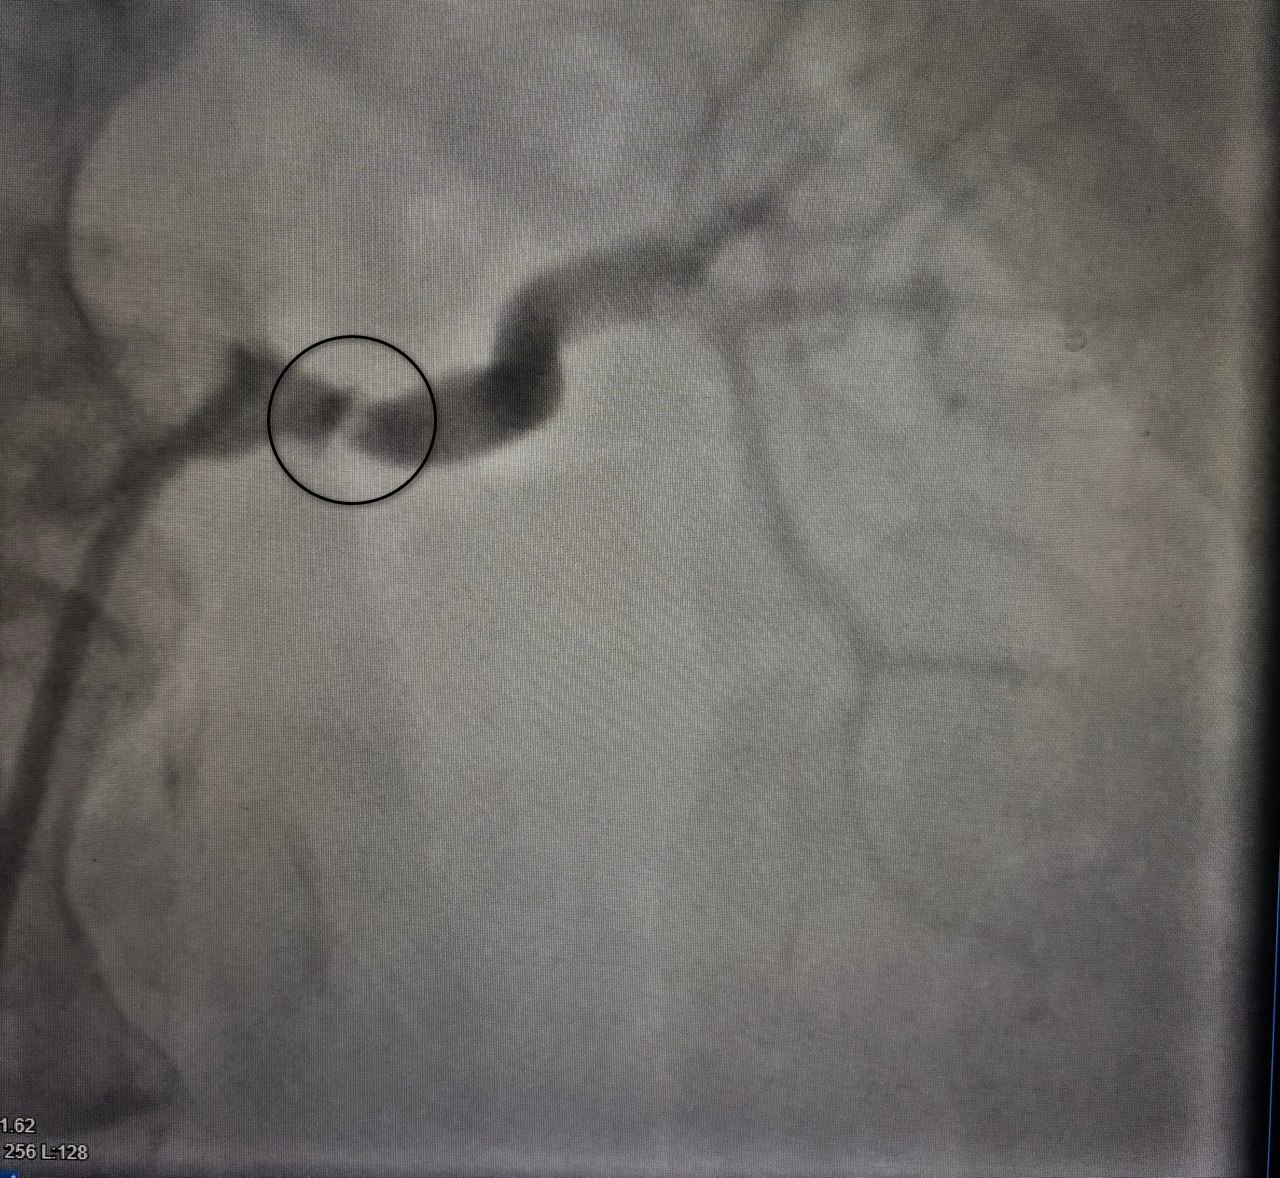

Под руководством заведующей отделением Ларисы Бородиной был проведен комплекс диагностических мероприятий. Ключевым исследованием стала КТ-ангиография брюшной полости, которая выявила критическое сужение (стеноз) левой почечной артерии. Именно эта патология, часто остающаяся нераспознанной, была причиной вторичной гипертензии, создававшей высокий риск повреждения почки и сердечно-сосудистых осложнений.

После постановки диагноза пациентку перевели в областную больницу №1, где под контролем врача-рентгенхирурга Ивана Тимошина ей выполнили баллонную ангиопластику и стентирование пораженной артерии. Это малоинвазивное вмешательство позволило восстановить кровоток. Состояние пациентки значительно улучшилось: давление стабилизировалось на нормальных значениях, что позволило снизить лекарственную нагрузку. Через год на профилактическом осмотре в Воронежской городской клинической больнице №3 она чувствовала себя хорошо, подтвердив долгосрочный успех лечения.